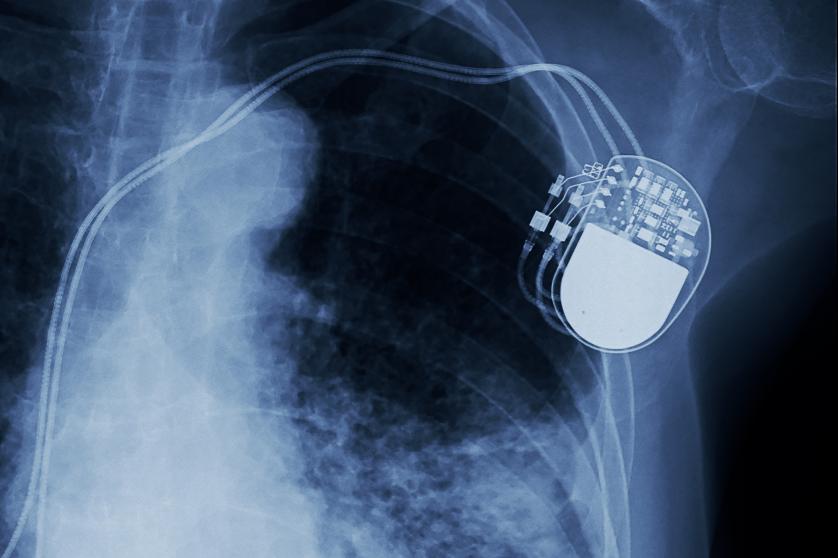

W 2017 po 20 latach UE dokonała przeglądu przepisów dotyczących wyrobów medycznych i diagnostyki in vitro, dotyczących ponad 500 tysięcy dostępnych dziś w UE urządzeń lub produktów medycznych, od prostych soczewek kontaktowych i plastrów, po zaawansowane technologicznie rozruszniki serca czy protezy. Celem zmian było m.in. zapewnienie wysokiego poziomu bezpieczeństwa i innowacji. Nie udało się jednak wdrożyć wydajnego systemu certyfikacji wymaganej dla dopuszczenia do stosowania.